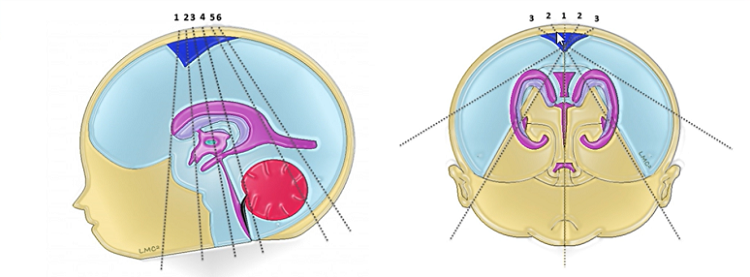

新生儿颅脑超声可以清晰显示新生儿颅内的各种结构及血管的情况。

正常颅脑超声

颅脑超声不仅适用于新生儿,还适用于前囟未闭的婴幼儿颅内病变的筛查及诊断,利用超声仪器通过小儿尚未闭合的囟门(前囟、侧囟、乳突囟、后囟,主要为前囟)对颅内结构及病变进行检查及诊断,可提示颅内病变的类型、程度、部位,可作为高危新生儿的常规筛查手段。

颅脑超声切面示意图